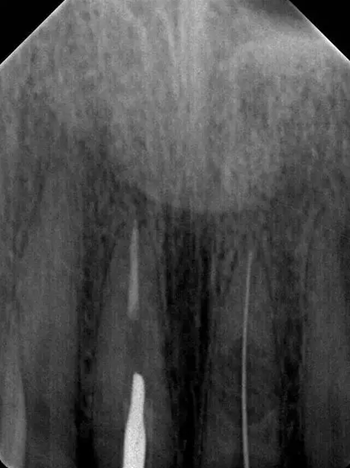

診斷:左上中切牙牙根內(nèi)吸收。治療計劃:左上中切牙根管治療,全冠修復(fù)。 治療過程:患者知情同意。使用含1/100,000腎上腺素的4%鹽酸阿替卡因(碧蘭麻,艾龍)局部浸潤麻醉,橡皮障隔濕。去腐未盡露髓,露髓孔出血多。開髓,使用10#不銹鋼K銼(MANI,日本)探查根管,根管中段有鈣化物阻擋,不能達到牙根全長(圖3A)。在顯微鏡下(Leica M400E,萊卡, 德國) 使用超聲尖(E1根管治療超聲尖,啄木鳥公司,中國)通開,采用根管長度測量儀(Root ZX, Morita公司,日本)加診斷絲片法(圖1B)測量根管長22 mm。使用控制扭矩馬達(X-smart,登士柏)和鎳鈦旋轉(zhuǎn)器械(Hero 642, Micromega)根管預(yù)備,根管預(yù)備過程中使用5.25%次氯酸鈉溶液沖洗。 根備完成后使用超聲蕩洗根管,5.25%次氯酸鈉溶液3 分鐘, 17% EDTA溶液1分鐘。干燥根管,使用螺旋充填器根管內(nèi)封氫氧化鈣糊,氧化鋅丁香油水門汀暫封。1周后患者復(fù)診,患者述無術(shù)后不適,檢查暫封完好,無叩痛,不松,牙齦無紅腫瘺管。使用橡皮障隔濕,去除暫封物,超聲蕩洗根管,5.25%次氯酸鈉溶液3 分鐘, 17% EDTA溶液1分鐘。干燥根管,牙膠尖(達雅鼎,中國)和必蘭根充糊劑(Cortisomol, 艾龍公司,法國)熱垂直加壓法根管充填。術(shù)后片顯示根充恰填,可見牙膠/糊劑被壓入鈣化物周圍和內(nèi)部縫隙內(nèi)